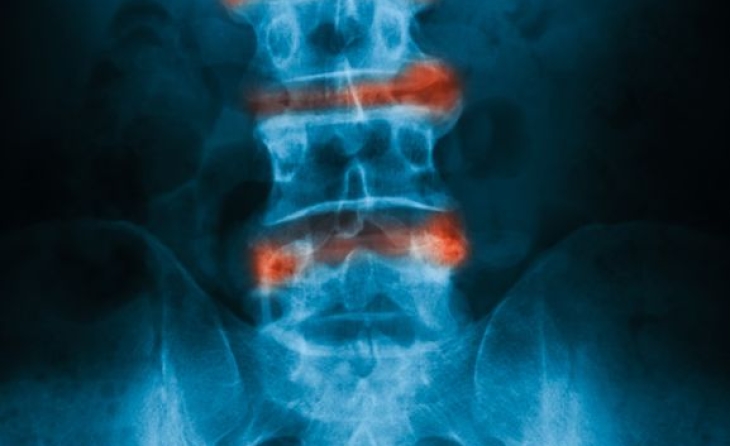

Πρόκειται για εγχύσεις διαλύματος τοπικού αναισθητικού και στεροειδούς στον επισκληρίδιο χώρο της σπονδυλικής στήλης. Τα στεροειδή είναι μια γενικότερη ονομασία για τα γλυκοκορτικοειδή. Το ενέσιμο στεροειδές είναι ένα τεχνητό συνθετικό φάρμακο που είναι παρόμοιο με την κορτιζόλη, μια φυσική ορμόνη που παράγεται στα επινεφρίδια και στον εγκέφαλο. Τα στεροειδή βοηθούν στη μείωση του πόνου και της φλεγμονής και χρησιμοποιούνται για τη θεραπεία ποικίλων φλεγμονωδών νόσων και επώδυνων καταστάσεων. Οι επισκληρίδιες εγχύσεις δύναται να πραγματοποιηθούν υπό υπερηχογραφική ή ακτινοσκοπική καθοδήγηση στην αυχενική, στη θωρακική και στην οσφυϊκή μοίρα της σπονδυλικής στήλης για αντιμετώπιση του πόνου από κήλη μεσοσπονδυλίου δίσκου ή στένωση του σπονδυλικού καναλιού.